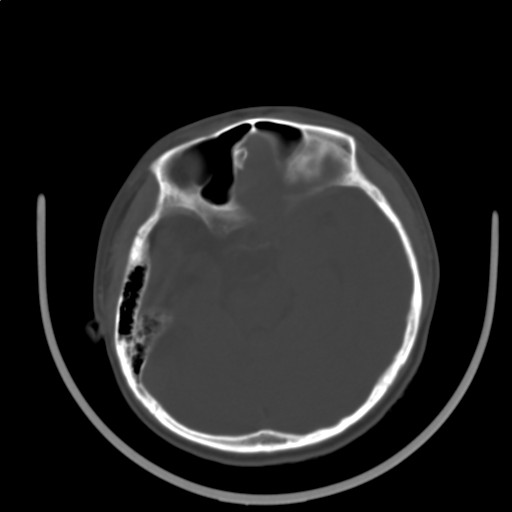

标题: PED3416:F,12Y,智力下降,学习成绩差,8个月时发过高烧。

右侧大脑发育不良伴动静脉畸形。

右侧半球萎缩,软化,多量脑回样钙化,考虑颅面血管瘤病,建议dsa检查

右侧半球萎缩,软化,多量脑回样钙化,同侧颅盖板障增宽,考虑颅面血管瘤病,建议dsa检查与化脓性脑膜炎后遗改变鉴别。